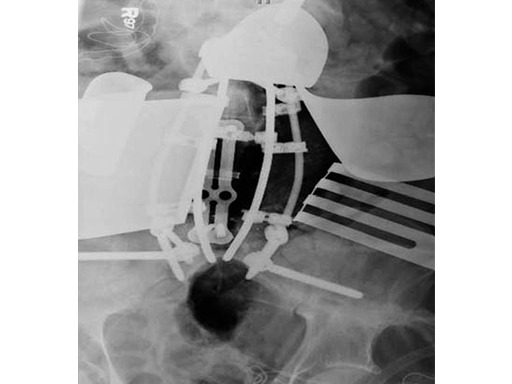

After discussing the risks of surgery, the patient consented to a staged posterior-anterior en bloc spondylectomy. The first stage involved a posterior lumbar pelvic exposure with dissection of the iliopsoas and lumbar plexus. Laminectomy of L3-L5 was performed, with instrumentation from L1 to the ilium bilaterally. Tomita saws were placed at the L3 and L5 disk space.

Stage two was a retroperitoneal exposure of L3-L5 with mobilation of the IVS, aorta, internal common illiac artery and veins, with en bloc resection of the tumor and partial L3 and L5 vertebrectomies.